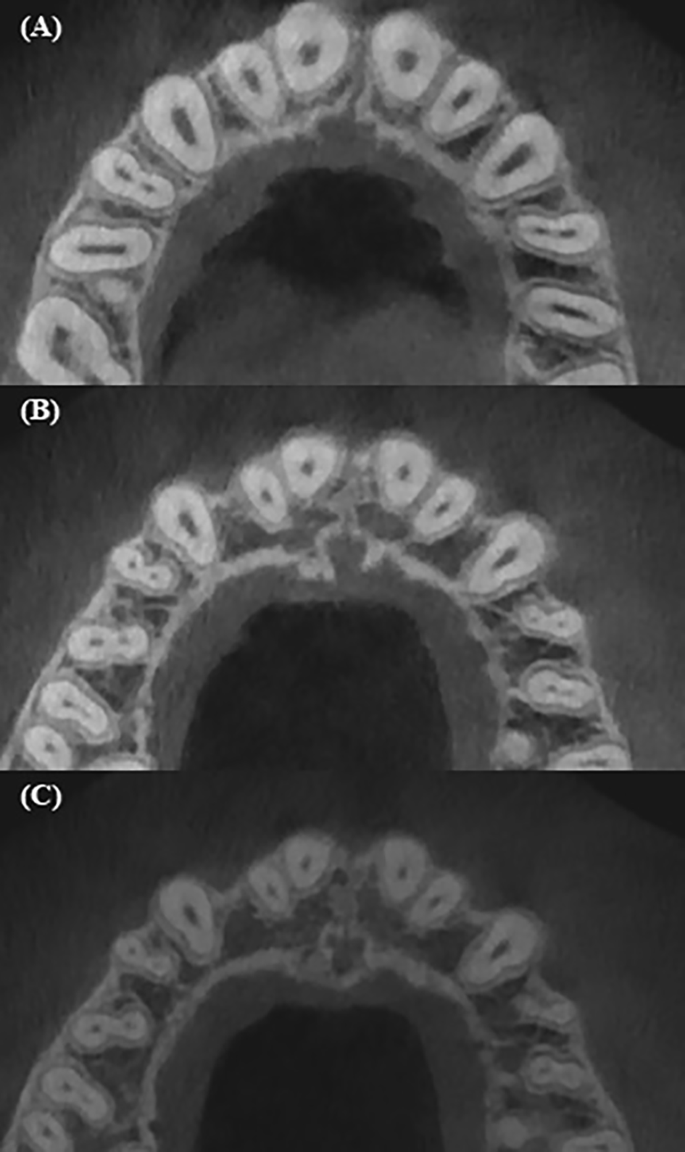

The study of root canal shape at the coronal, middle and apical parts showed that the shape is not constant; it changes depending on the number of canals in the root, the presence or absence of isthmuses. When analysing the maxillary anterior teeth, it was found that the shape of the central and lateral incisors in the upper jaw in 100% is round throughout its entire length (Table 1). The canines of the upper jaw and low jaw are characterized by an oval shape in 100%, which is preserved throughout its entire length (Table 1; Fig. 1). An analysis of the root canal shape of maxillary first and second two-rooted pre-molar showed that in the coronal third round shape was in 37.7% of cases, and oval in 62.3%. In the single-rooted maxillary premolars, in the coronal third, an oval shape, a ribbon-like type 1 and ribbon-like type 5 were revealed. In the middle and apical thirds, the ribbon-like type 1 changes into ribbon-like type 5 (Table 2; Figs. 1 and 2). In the maxillary molars, In MB in the coronal and middle thirds, a ribbon-like type 1 was detected and changed to oval or round in some cases in the apical third (Table 3; Fig. 2).

The mandibular central and lateral incisors are characterized by an oval shape of the root canal, which does not change throughout its entire length in 99% (Table 4; Fig. 3). In the mandibular premolars, the oval shape was found to change in some cases to round or ribbon-like in the apical third (Table 5). For mandibular molars the distal root was found to have an oval or ribbon-like shape of the 1st and 5th types, which changed in some cases in the apical third. For the mesial root in the coronal third ribbon-like shape of the 1st and 2nd types were observed. In the middle third, the number of type 1 ribbon-like decreased by 7 times and they were not detected in the apical part, while the number of ribbon-like of the 5th type in the middle and apical thirds has increased (Table 6; Figs. 4 and 5).